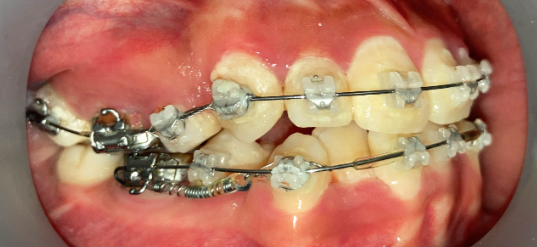

抜歯矯正1年後の口腔内|奈良の矯正歯科

治療1年後

他院で非抜歯矯正を受けたものの、口元の突出感が改善せず来院。精密検査の結果、上下4本の抜歯が必要と判断し、ワイヤー矯正でやり直しました。